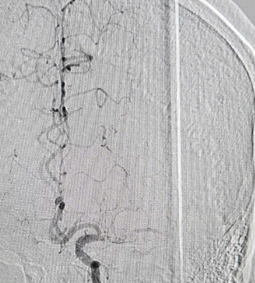

Hình ảnh tái thông mạch não sau can thiệp lấy huyết khối

Lấy huyết khối cơ học là phương pháp điều trị tái tưới máu bằng cách loại bỏ cục máu đông trong lòng mạch bằng các dụng cụ theo phương pháp cơ học qua đường can thiệp động mạch. Can thiệp lấy huyết khối đường động mạch trong cửa sổ 6 giờ được chấp nhận trong khuyến cáo của AHA/ASA năm 2015 và cửa sổ mở rộng 6 -24 giờ trong khuyến cáo năm 2018.